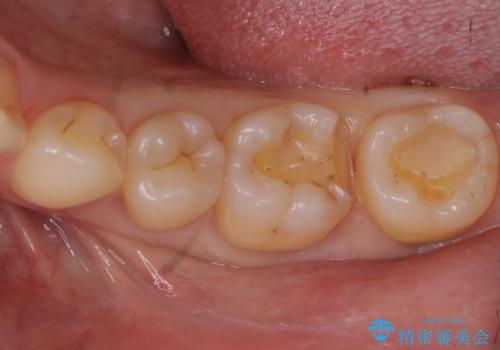

治療途中で放置した奥歯 セラミックインレーでの修復

- 「他の医院で治療していたものの途中で放置していた奥歯が欠けたから治してほしい」とのことで来院。

セラミックでの治療を希望されたため、詰められている樹脂の材料を除去してからセラミックインレーでの修復を行いました。